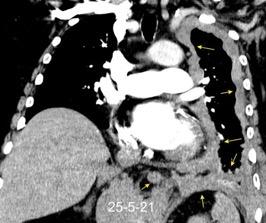

Síndrome de afectación postcardiaca (postcardiac injury)

Post infarto 1-7 % (Dressler)

Trauma cerrado Implantación marcapasos

Cirugía cardiaca. 17-31% (Post.pericardiotomía)

3707 pacientes 29 Derrames (0,78%) > de 25% del hemitórax

Todas menos 2 Izdos.

Angioplastia

By-pass coronario 21-10-03